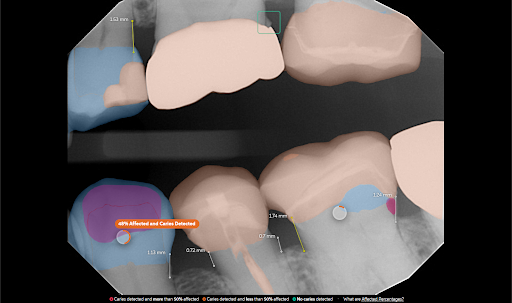

The Affected feature calculates the percentage of the healthy crown impacted by various conditions, helping support both diagnostic documentation and insurance claims.

These factors are combined into a single percentage value commonly referred to as DMF (Decayed, Missing, Filled).

A color-coded radial chart displays the affected percentage.

A legend explains what each color indicates.